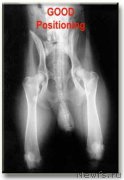

ньюф-не-чайница Здесь явный подвывих сустава. Вероятнее всего С или D

И второй вопрос-а правильно ли положена собака?

И второй вопрос-а правильно ли положена собака?

Собака положенна практически правильно.

Собака уложена правильно. Немного перекошены тазовые кости, но это не принципиально. Нет смысла делать снимки лягушкой. Сложно зафиксировать правильно собаку

Собака уложена правильно. Немного перекошены тазовые кости, но это не принципиально. Нет смысла делать снимки лягушкой. Сложно зафиксировать правильно собаку

А мне кажется подвывих на правой лапе, где R стоит, и не сильный.

Вертлюжные впадины не разбиты и ярко выражены, но не закрыты, головка бедренной кости не деформирована, но не прижата плотно, чуть наклонено правое крыло таза, но не сильно.

Двигаться должна нормально, если и беречь, то правую лапку, это видно хорошо по походке.

Снимок странный, как наложенный, хвостовые позвонки почти не видно и в сторону ушли.... Или мне так кажется, не то что тоо

Вертлюжные впадины не разбиты и ярко выражены, но не закрыты, головка бедренной кости не деформирована, но не прижата плотно, чуть наклонено правое крыло таза, но не сильно.

Двигаться должна нормально, если и беречь, то правую лапку, это видно хорошо по походке.

Снимок странный, как наложенный, хвостовые позвонки почти не видно и в сторону ушли.... Или мне так кажется, не то что тоо

Цитата от ньюфо-мама (источник):А мне кажется подвывих на правой лапе, где R стоит, и не сильный.Нужно чтобы врач описал..., а то сколько людей столько и мнений. Я вижу, что вертлужная впадина достаточно сильно уплощена и головка бедра тоже изменена, вероятно - D.

Вертлюжные впадины не разбиты и ярко выражены, но не закрыты, головка бедренной кости не деформирована, но не прижата плотно, чуть наклонено правое крыло таза, но не сильно.

Двигаться должна нормально, если и беречь, то правую лапку, это видно хорошо по походке.

Снимок странный, как наложенный, хвостовые позвонки почти не видно и в сторону ушли.... Или мне так кажется, не то что тоо

Врач сказал, что на снимке артефакт, или сбой, или наложение, такого быть не может, это относительно писюна и яичек, они не контрастны и не должны быть видны на рентгене, тем более в этом месте.

По ТЗБ, да правый плохой совсем, да и левый не очень, но больше смутили коленные суставы, сильный выверт бедренной кости относительно большеберцовой, может разрыв или растежение крестовидной связки, не так выглядит коленный сустав, другой разворот.

Смимок однозначно некорректный, нужно переделать и врач готов дать консультацию по телефону, но по новому снимку, и снимку коленного сустава в другой проекции.

По ТЗБ, да правый плохой совсем, да и левый не очень, но больше смутили коленные суставы, сильный выверт бедренной кости относительно большеберцовой, может разрыв или растежение крестовидной связки, не так выглядит коленный сустав, другой разворот.

Смимок однозначно некорректный, нужно переделать и врач готов дать консультацию по телефону, но по новому снимку, и снимку коленного сустава в другой проекции.

1- остатки купированного хвоста

2 - позвоночник собаки "донора"

3- видны контуры наложения снимка другой собаки. Специально не стала обводить тык-в-тык, чтобы было видно

4 - смещение линии наложенного позвоночника на позвоночник "донора"

И очень хотелось бы посмотреть на ТАКОЙ хвост ньюфа, тем более 3-летнего, да еще и "крючком" под наркозом.

Я ни в коей мере не собираюсь обсуждать степени дисплазии, но то, что снимок "подложный", да еще и не очень тщательно отработанный фотошопом - сомнений не вызывает.

Мне моим дилетантским взглядом видится небольшой завал на какой-то из боков (даже не могу определить на какой. Оттого и перекос тазовых, и уход от центра позвоночника с хвостом) и недостаточный оттяг вниз задних лап из-за чего бедро кажется короче (с перекачанными мышцами как кто-то упомянул), мошонка длиннее, а коленные суставы деформированными.

Мне моим дилетантским взглядом видится небольшой завал на какой-то из боков (даже не могу определить на какой. Оттого и перекос тазовых, и уход от центра позвоночника с хвостом) и недостаточный оттяг вниз задних лап из-за чего бедро кажется короче (с перекачанными мышцами как кто-то упомянул), мошонка длиннее, а коленные суставы деформированными.

Дело в том, что если очень внимательно приглядеться при большом увеличении, то видно, что у собаки как бы два позвоночника - один уходит в купированный хвост (это не мошонка, это купированный хвост, мошонка на рентгене НИКОГДА не будет видна в таком виде). Тогда вообще непонятно, откуда взялся хвост и совсем не ньюфовский. А уж с какими целями - это вообще не ко мне.